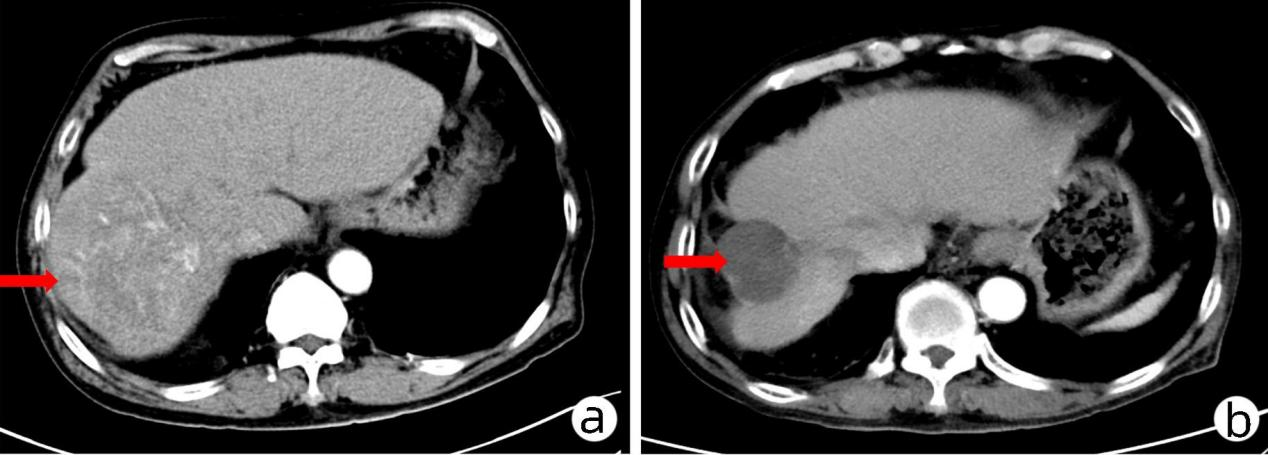

因HAIC独特优势,对于肝癌伴门静脉癌栓(尤其是主干癌栓)、明显或广泛动-静脉瘘、TACE不能良好栓塞巨大肿瘤及多次TACE治疗产生抵抗的肝癌患者,效果客观。2020年欧洲肿瘤内科学会上石明教授团队牵头的一项III期研究显示HAIC-FOLFOX对比 TACE治疗大肝癌具有更高的ORR(45.9% vs 17.9%)和手术转化率(23.9% vs 11.5%)、更长的总生存期OS(23.1个月vs 16.07个月)和无进展生存期PFS(9.63个月vs 5.4个月)。